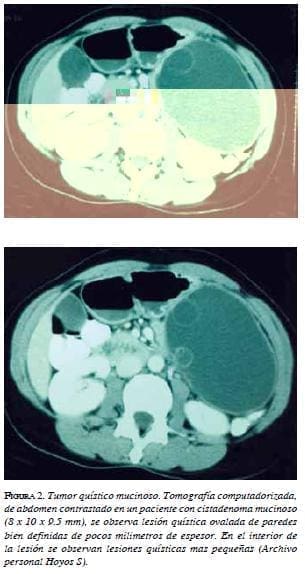

En la tomografía computadorizada, las neoplasias quísticas mucinosas se evidencian como lesiones hipodensas rodeadas de parénquima pancreático. Se encuentra que los quistes, usualmente, tienen una forma redonda. La lesión, generalmente, se aprecia bien circunscrita y con morfología blanda. Pueden observarse, además, calcificaciones curvilíneas en la periferia de la lesión o en su interior. Luego de la infusión del material de contraste, se observan tabiques o quistes murales en la pared quística. La presencia de tabiques y calcificaciones sugieren un proceso maligno.

La presencia de tabiques, calcificaciones, múltiples lóbulos y proyecciones papilares se asocia frecuentemente con un proceso maligno 25 (figura 2).